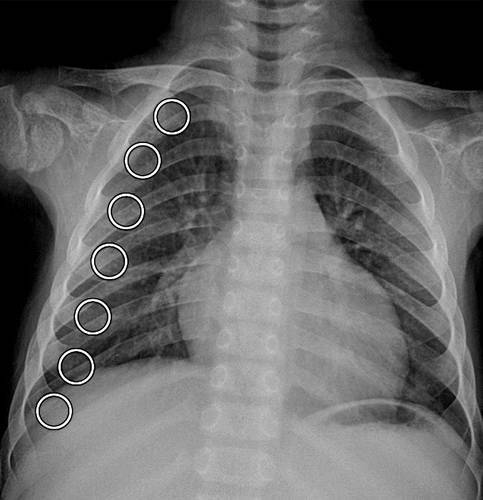

椎までの左側横突起のほほ中央に骨折を認め,骨折片 の転移は第謡曲突起の場合に最も著しく第iv,第1の 場合がこれに次ぎ第工,第vε順序である.第iv腰椎 右側横突起の中央にほぼ垂直の骨折線が認められるが 転移はない.椎体棘突起には骨折,脱臼は認